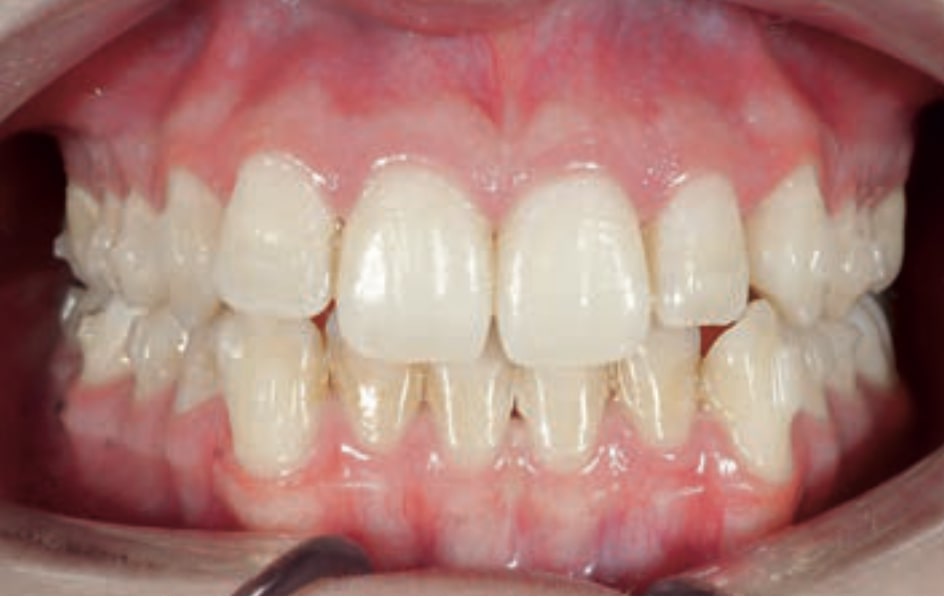

Chief complaint: The patient, a 19-year-old woman, was evaluated to undergo orthodontic treatment using the Angel Aligner Pro system. She presents with a skeletal Class III, mesofacial, with a dental Class III malocclusion and a 2 mm deviation of the lower midline to the left. Teeth 33 and 43 are out of the arch and cortical bone, with a crossbite issue on tooth 33. Fortunately, no functional issues affecting swallowing or breathing have been detected. The patient’s motivation for starting treatment was a general review of her dental and aesthetic health. The soft tissue analysis reveals mandibular protrusion that influences her facial profile. This diagnosis highlights the need for a comprehensive approach to address dental and skeletal misalignments, improving both the patient’s functionality and facial aesthetics.

• Dental Class III, 2 mm deviation of the lower midline to the left. 33 and 43 out of the arch and the cortical bone.

• Crossbite of 33.

Treatment plan

• Distalize third and fourth quadrant

• Solve the cross bite of 33.